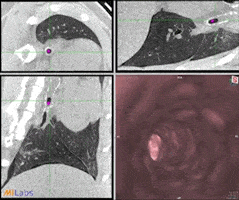

High-resolution detailed ferret CT-lung imaging with virtual endoscopy.